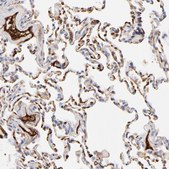

immunohistochemistry: 1:200- 1:500

The Human Protein Atlas project can be subdivided into three efforts: Human Tissue Atlas, Cancer Atlas, and Human Cell Atlas. The antibodies that have been generated in support of the Tissue and Cancer Atlas projects have been tested by immunohistochemistry against hundreds of normal and disease tissues and through the recent efforts of the Human Cell Atlas project, many have been characterized by immunofluorescence to map the human proteome not only at the tissue level but now at the subcellular level. These images and the collection of this vast data set can be viewed on the Human Protein Atlas (HPA) site by clicking on the Image Gallery link. We also provide Prestige Antibodies® protocols and other useful information.

- IHC tissue array of 44 normal human tissues and 20 of the most common cancer type tissues.